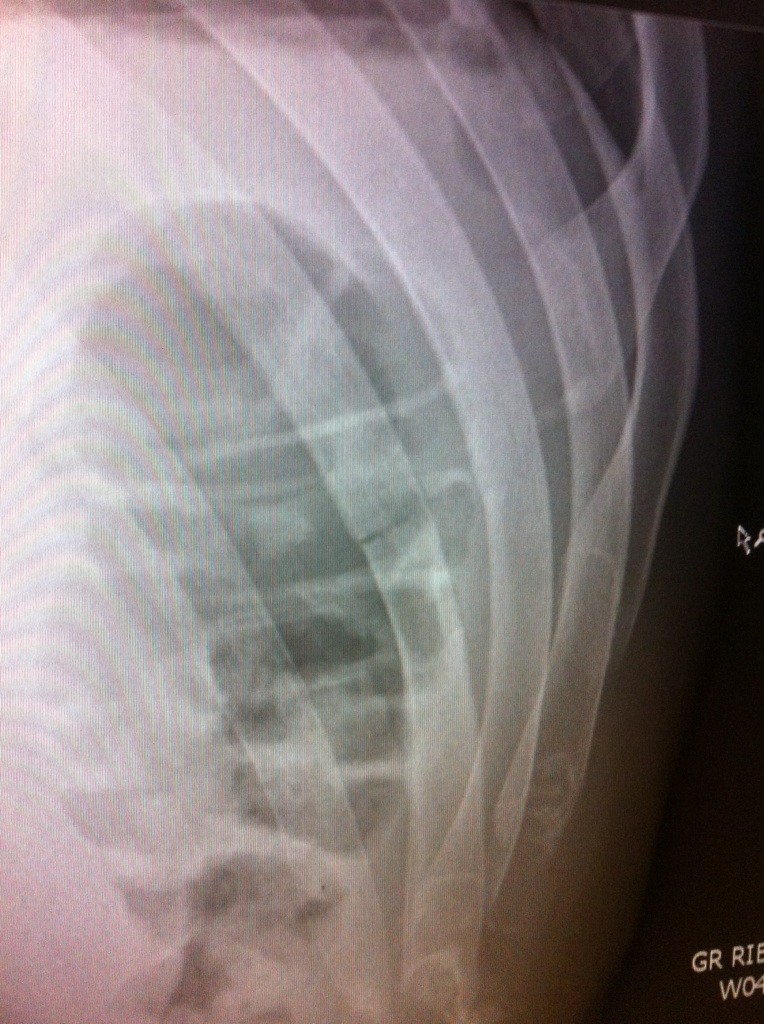

Heute Morgan „Twittert“ Faber nun folgendes Röntgenbild, wo die betroffenen Rippe deutlich zu erkennen ist.

„Congrats 2 RenanBarao. He’s a tough dude. Broke my rib in the 1st with a great knee. Thank u 4 all the support“ so fügt Faber der Bildbeschreibung hinzu.